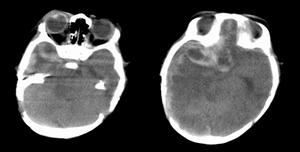

腦幹出血症腦幹出血也叫橋腦出血:橋腦是腦幹出血的好發部位。早期表現病處側面癱,對側肢體攤,稱為交叉性癱。這是橋腦出血的臨床特點。如果出血量大,則影響對側,出現四肢癱、瞳孔縮小、高熱、昏迷等症;如果血液破入第四腦室則出現抽搐、呼吸不規則等嚴重症狀

腦幹出血多由高血壓導致基底動脈中央支破裂引起,往往在數秒到數分鐘內引起昏迷,可立刻昏迷、四肢癱、針尖樣瞳孔,數小時內死亡;水平眼球運動受累而垂直眼球運動佳,有的病例可以出現眼球上下跳動。對側眼球出現5秒間隔的遊動。病又往往出現四肢癱,去大腦強直。有時可以出現中樞性高熱、呼吸異常。出血可破入四腦室,血腫向腹側擴展,導致居中的固定瞳孔,小的基底部出血可引起“閉鎖綜合徵”;未累及上行網狀激活系統的小出血常常沒有嚴重神經功能缺失,症狀輕微,預後良好。

腦出血繼發丘腦下部損傷:①丘腦下部的解剖特點:丘腦下部包括丘腦下溝以下的第三腦室壁及室底上的一些結構,其中含有15對以上的神經核團,數以萬計的神經分泌細胞,如位於第三腦室壁上的室旁核、空周圍核、腹內側核、背內側核等,丘腦下部長約1cm,重約4g,約為全腦重量的3‰.但機制複雜,與植物神經、內臟活動。內分泌、代謝、情緒、睡眠和覺醒均有關。該區還有以下特徵:有豐富的毛細血管網,較腦的其他部分多一倍以上,且該處血腦屏障不夠健全,有較高的通透性,故在缺氧、中毒,顱壓增高、感染等損傷時易出現水腫和出出血等改變;漏斗柄是丘腦下部與垂體間的神經纖維聯繫,當其受壓、腫脹、出血時,該聯繫即遭到破壞。②丘腦下部損傷的臨床症狀:腦出血引起顱內壓增高,出現占位效應,致使丘腦下部受壓,垂體柄水腫、移位、扭曲等,加以繼發腦室出血損傷第三腦室壁均累及丘腦下部,出現症狀,常表現為出血性胃糜爛或潰瘍,嘔吐咖啡樣胃內容物,急性肺水腫,白細胞增高.血糖升高,中樞性高熱,大汗淋漓等。

腦出血繼發腦疝;腦出血可以並發天幕疝,中心疝、枕骨大孔疝、蝶骨嵴疝、扣帶回疝及小腦上疝。後三者一般不出現明顯的臨床症狀,多在剖檢時發現;前三者臨床症狀明顯,多為症狀加重或致死的原因。天幕沿時出現同側瞳孔散大。中心疝時雙側瞳孔均小呼吸不規則。其病理標誌為:①赤質、紅核向下移位,②第三腦室向下移位,(3)丘腦下部及上部腦幹向下移位。出現中心疝時,則很可能發生枕大孔疝,呼吸心跳解離,至死亡。